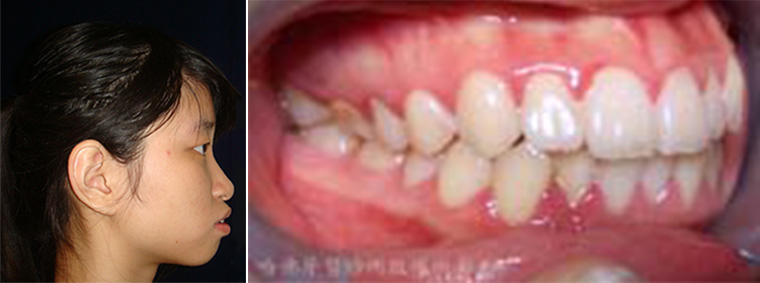

「齒列不整」就像是近視眼一樣,是個普遍常見的異常生理特徵。有些人會坦然接受它的存在,在生活中與它共存。然而也有一些人會去接受矯正治療,修正「齒列不整」。「齒列不整」到底會引發什麼樣的傷害呢(圖1)?

(圖1)「齒列不整」就像是近視眼一樣,是個普遍常見的異常生理特徵。有些人會坦然接受它的存在,在生活中與它共存。然而也有一些人會去接受矯正治療,修正「齒列不整」。「齒列不整」到底會引發什麼樣的傷害呢?